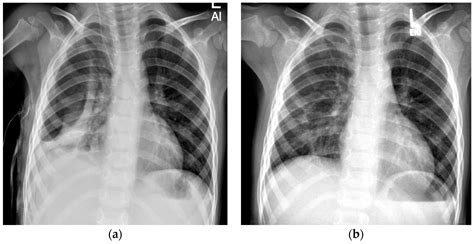

• Chest X-ray: This is the primary diagnostic tool for pneumothorax. A chest X-ray can show the presence of air in the pleural space and the extent of the lung collapse.

• Observation: In mild cases, the healthcare provider may choose to monitor the infant closely without immediate intervention. The pneumothorax may resolve on its own as the air is gradually reabsorbed.